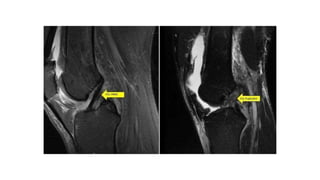

• MRI is a non-invasive method of diagnosing ligament injuries, and may be

of use in doubtful cases

• MRI is a non-invasive method of detecting meniscus tears.

• It is a very sensitive investigation, and sometimes picks up tears which are of no clinical